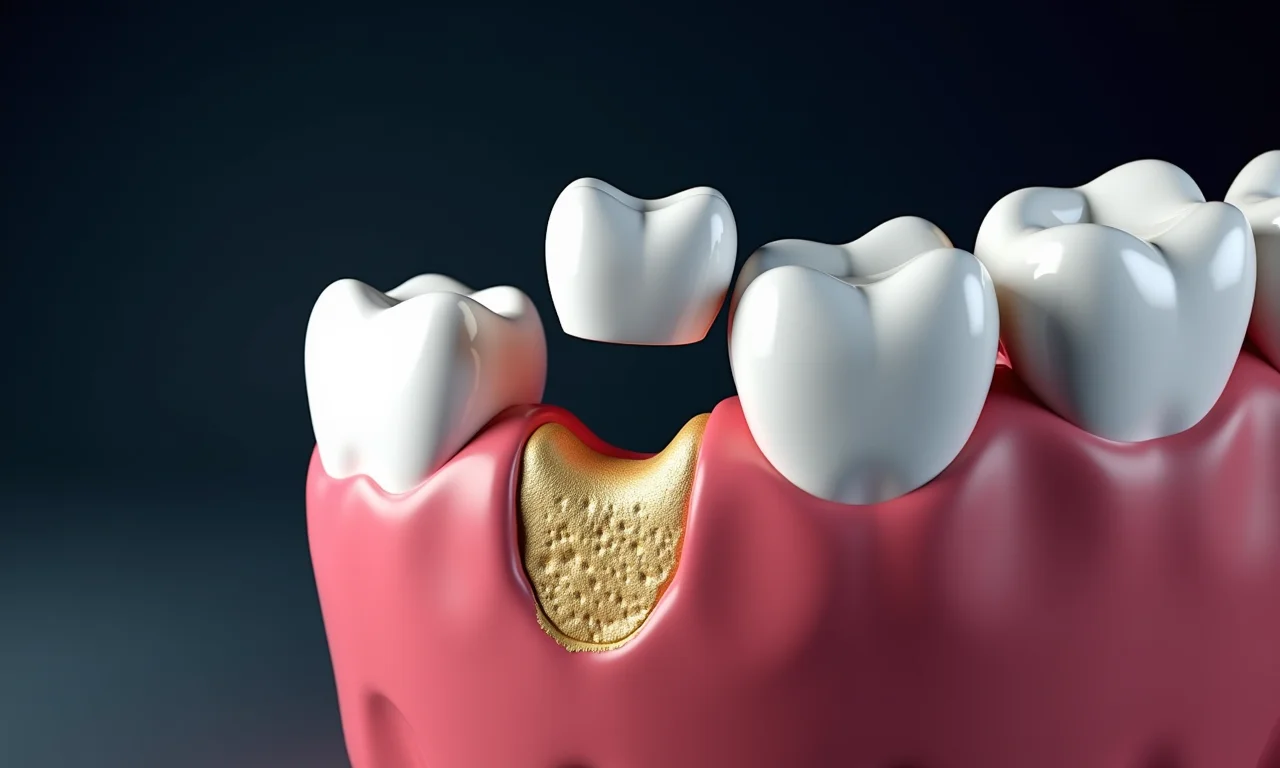

Falta de Espaço na Arcada

Quando não há espaço suficiente, o siso pode empurrar os outros dentes, causando desalinhamento e apinhamento. Isso pode comprometer a estética do sorriso e dificultar a higiene bucal. Imagina só a confusão!